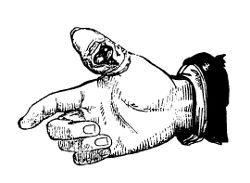

| Paronychia or Whitlow | 396 |